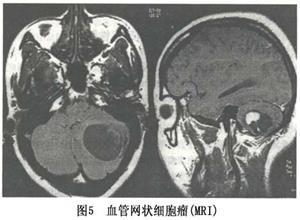

血管网织细胞瘤

简介血管网织细胞瘤(Angioreticuloma)有人称之为血管母细胞瘤为良性肿瘤,占颅内肿瘤 的1.3%~2.4%。男性多于女性,约为2:1,多见于青壮年。本病有遗传倾向,临床症状示肿瘤位置和性质而异,患者多合并有其他脏器的血管瘤性病变或红细胞增多症,视网膜和脑内同时发生肿瘤者称Von Hippel Lindau病。